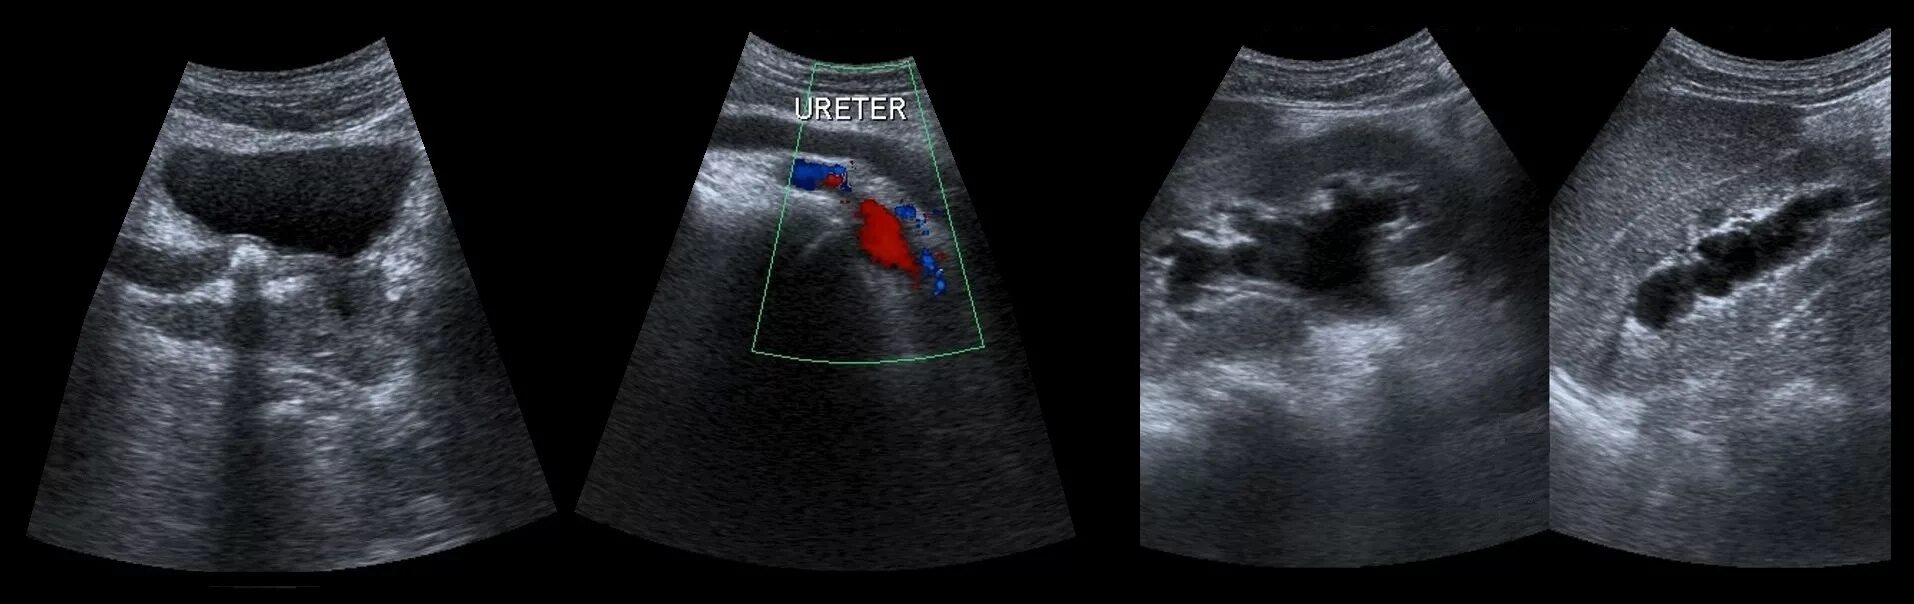

Узи шип